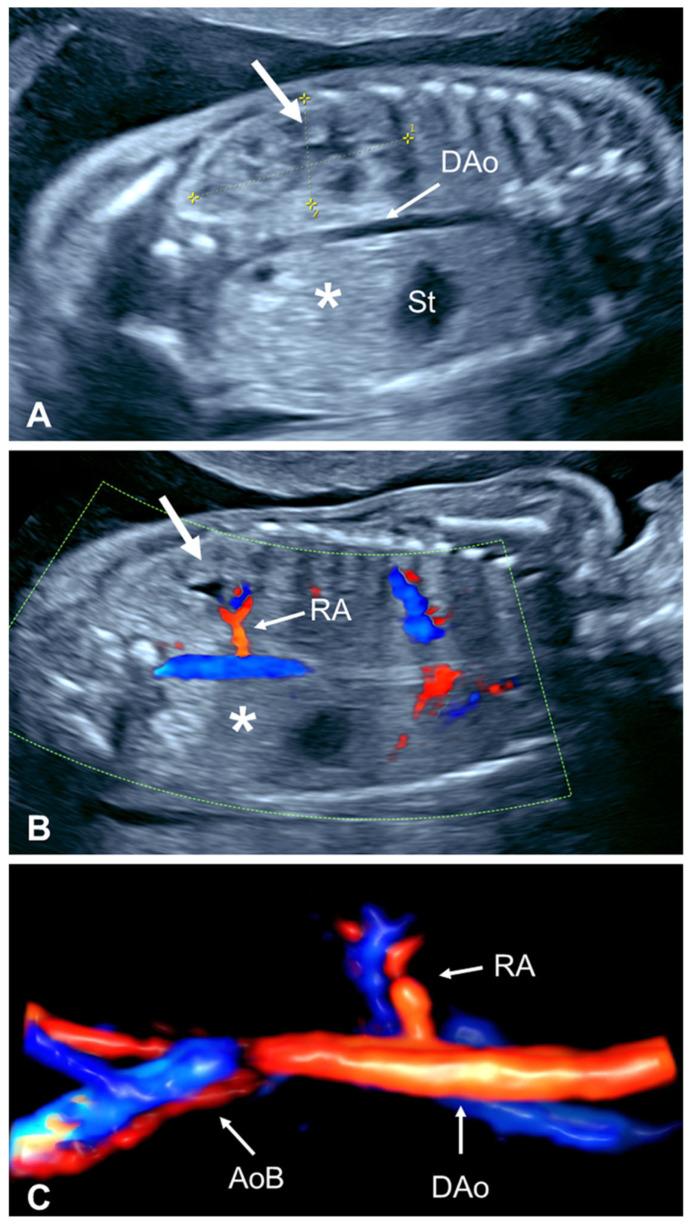

单侧肾缺如:产前诊断与产后问题

Unilateral renal agenesis (URA) is a urinary tract congenital anomaly characterized by a congenital absence or early developmental arrest of only one kidney. In the presence of a normal contralateral kidney, URA is typically considered a condition of minimal clinical significance as the solitary kidney often undergoes hypertrophy and can sufficiently perform the needed renal function after birth. However, postnatal studies suggest that URA has a significant association with other urinary and extra-urinary anomalies and may have implications for long-term health. This descriptive review focuses on the perinatal aspects of URA, emphasizing the main ultrasound findings to establish the prenatal diagnosis and to guide perinatal management. The pediatric implications of this diagnosis, particularly the high prevalence of long-term complications including hypertension, proteinuria, and a decreased glomerular filtration rate, are also briefly reviewed. URA is consistently associated with other ipsilateral urogenital anomalies. In females, there is a significant association with uterine anomalies that has significant implications for subsequent reproductive function. In males, the prevalence of both urinary and genital anomalies is also increased, which may also have implications for future fertility. Prenatal ultrasound offers the possibility of early diagnosis and parental counseling, which may result in timely intervention to reduce contralateral renal damage, prevent severe urogenital manifestations and co-morbidities, and improve fertility and the quality of life.

单侧肾缺如(URA)是一种泌尿系统先天性异常,其特征为仅一侧肾脏先天性缺失或早期发育停滞。在对侧肾脏正常的情况下,URA通常被认为临床意义不大,因为单肾常发生肥大,出生后能够充分履行所需的肾功能。然而,产后研究表明,URA与其他泌尿系统及泌尿系统外异常显著相关,可能对长期健康有影响。本描述性综述聚焦于URA的围产期情况,着重介绍用于产前诊断及指导围产期管理的主要超声检查结果。还简要回顾了该诊断对儿科的影响,尤其是包括高血压、蛋白尿和肾小球滤过率降低在内的长期并发症的高发生率。URA始终与其他同侧泌尿生殖系统异常相关。在女性中,与子宫异常显著相关,这对后续生殖功能有重大影响。在男性中,泌尿系统和生殖系统异常的发生率也会增加,这可能对未来生育能力也有影响。产前超声检查提供了早期诊断及向父母咨询的可能性,这可能带来及时干预,以减少对侧肾脏损害,预防严重的泌尿生殖系统表现及合并症,并提高生育能力和生活质量。